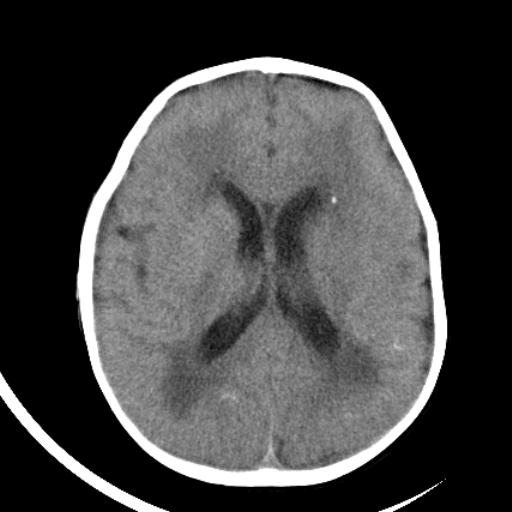

双侧脑室前后角周围白质片状低密度影,双侧侧脑室旁、双顶叶皮层及皮层下多个小原点状钙化灶,不除外torch感染。右顶叶脑回似乎较对侧大,建议mri检查以除外脑发育异常。

考虑:1、巨脑回畸形(皮质明显增厚+脑回明显增宽+白质减少)。

2、torch综合征(室管膜下钙化+白质内及皮髓质交界处多发钙化)。